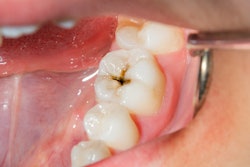

Fluorosis can cause white lines and blurred areas on teeth, as well as more severe staining and pitting. When treating generalized fluorosis with tooth surface defects, unsupported and pitted enamel or dentin tissue needs to be removed and then restored. In the new study, ceramics laminates showed long-term success in restoring the smile of patients with advanced fluorosis.

To evaluate the success rate and estimated survival of porcelain laminate veneers in teeth with anterior fluorosis, the researchers conducted a retrospective study of 358 veneers. The veneers covered the incisal edge and part of the palatal/lingual side of the tooth with a 1-mm-high palatal bevel.